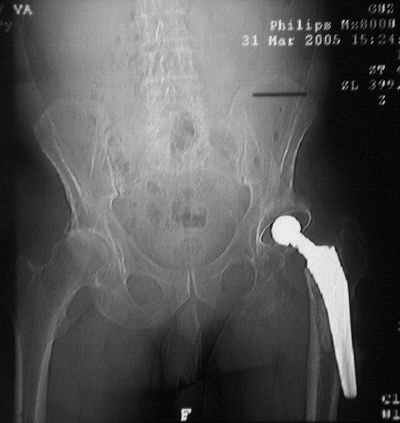

Уважаемые коллеги,Мужчина, 69 лет, в декабре 2004 г перенес тотальную цементную артропластику . Через 3 мес после операции на фоне прогрессирующих болей в средней и проксимальной третях бедра при нагрузке возникли резкие боли и появилось опухолевидное болезненно образование. Процесс сопровождался резким одномоментным укорочением ноги.

В феврале 2005 г. выполнена ревизионная артропластика, завершившаяся прогрессировавшим в течение 1-2 мес укорочением ноги. В настоящее время ходит только с костылями, при движениях в тазобедренном суставе испытывает резкие боли, ощущает хруст. Попытка осевой нагрузки бедра сопровождается ощущением "перемещения поршня" и заметным по внешним ориентирам укорочением левой ноги на 1-1,5 см.

Наверное перфорация стенки при первичном протезировании и неадекватный размер Вагнера при ревизионном? Что-нибудь еще?

Я полностью поддерживаю Ваше мнение об интраоперационной перфорации при первичном протезировании, т.к. при внимательном рассмотрении рентгенограммы после этого этапа виден дефект кортикального слоя именно по задне-наружной поверхности .